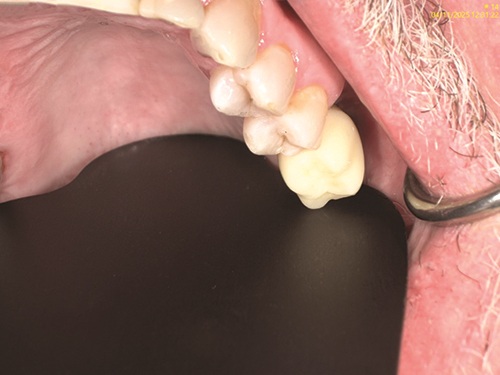

This case involved a 45-year-old male who lost tooth #14 because of periodontal disease, and after extraction, lost bone support to place an implant in the site. The patient had no provisional appliance but was ready for a permanent solution to the missing first molar. The patient had a thick biotype; hard and soft tissues were within normal limits, with no popping or clicking of the temporomandibular joint and no pain from the muscles of mastication. Maximum opening was 40 mm. A CBCT was taken to determine any anatomical structures of concern, if any buttress was present that would make the sinus lift more difficult, and if any anatomical structures were present in the lateral wall of the sinus (the anterior branch of the superior anterior artery PSA). On evaluation, it was found that the height was inadequate at 1.4 mm, the width was adequate at 8 mm, and the depth was also inadequate (Figs. 1 and 2). Thus, implant placement would be compromised. The use of osseodensification drills was contraindicated, as there was inadequate bone to perform a vertical sinus lift without tearing the sinus membrane, with an elevation of 7–10 mm. Thus, a lateral sinus wall approach was indicated to gain sufficient height for placement of an implant at least 10 mm in length.

Fig. 1